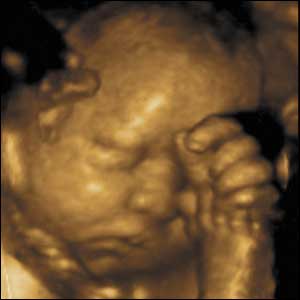

22 weeks gestation, 21 cm from crown to rump.

3 of 10

At 22 weeks gestation babies are capable of fine hand and finger movements. In a short space of time this baby scratches, rubs and pats his cheek before doing the same to his nose.